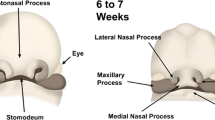

The complex embryological development of the nose with a close relation, interaction and finally separation of the neuroectoderm, mesoderm and surface ectoderm has been extensively studied, and many embryogenetic theories have been proposed [4, 5, 6, 7, 8, 18, 19, 21].

Despite the fact that currently no final consensus concerning the normal nasal development has been achieved, NDSC, nasal gliomas and encephaloceles are believed to share similar embryogenetic origins [7, 18, 19, 20, 21]. A failure of the normal separation of the different germ cell layers is considered to be causative. Consequently, all patients with developmental nasal masses must be considered as potentially having an intracranial extension [7, 18, 19, 20, 21]. Because surgical extirpation is considered to be the only method of managing patients with these lesions [2, 4, 19, 22, 23], a careful examination and radiological imaging is essential to determine the correct surgical procedure and to avoid complications.